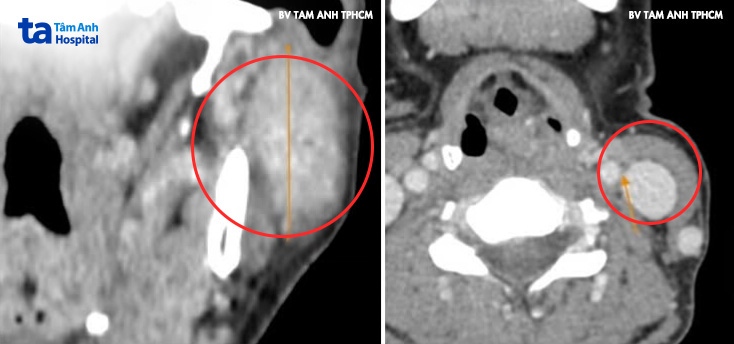

Trước đó một năm, chị Dương từng nổi một u nhỏ ở góc hàm mang tai trái song không đau, không tăng kích thước nên chị không đi khám. Gần đây, mặt chị tự nhiên mất cân đối, hàm trái hơi to hơn hàm phải nên chị đến khám tại Phòng khám Đa khoa Tâm Anh Quận 7. BS.CKI Võ Bá Thạch, Đơn vị Tai Mũi Họng, cho biết kết quả chụp CT và siêu âm ghi nhận khối u kích thước dài hơn 4 cm chiếm gần hết mô tuyến mang tai trái, phát triển vào trong, xâm lấn tĩnh mạch sau hàm. Cạnh trước khối u nghi có hạch gần 1 cm và hai hạch hơn 1 cm vùng cổ.

Kết quả sinh thiết là u tuyến mang tai hóa bọc. Đánh giá trên lâm sàng và hình ảnh học, bác sĩ tiên lượng u tuyến mang tai ở cả thùy nông và thùy sâu, khả năng rất cao là u ác tính, đã di căn hạch cổ. “Tuy nhiên để chẩn đoán chính xác cần phải phẫu thuật lấy bệnh phẩm và giải phẫu bệnh”, bác sĩ Thạch nói.